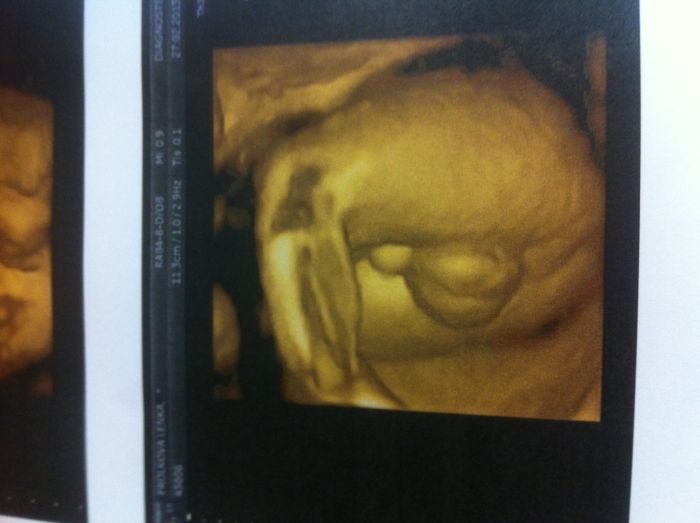

Tak posilam fotecky Manolita, na jedne ma vyplazlej jazyk, na druhe je videt jeho chlouba ( holky taky se Vam zda tak velka jako nam ;)???? ) a na jedne je vaznej.

Chacha, a to se manzel pta toho ultrazvuk. doktora jestli se mu nezda ze ma ty kulicky nejaky vetsi a dr. se na me podiva a rika, no tak snad geny, ne, to bude po tatinkovi. Tak jsem v tu chvili nahodila usmev a Manuel na to ,, no samozrejme,,....... A ja si v duchu pomyslela, ze to urcite, ze to bude spis po dedeckovi Fanooosovi dvoumetrovym z Brna ;D.... No ale manzela v tom necham, je stastnej ze je syn vyvinutej a vsude to ukazeje, uz je s tim fakt jak blebej.

No Leni jsem ráda, že jsi se ozvala :-) Manolito je teeeda chlapisko ani se nemohu vyjádřit nad jeho chloubou , protože k takovému miminku by to bylo až neslušné snad

Leni :-D úplně to vidím jak se chlubí jaký má kluk už v břichu koule:-D to mě fakt podrž oni na nic jinýho snad ani nemyslí.